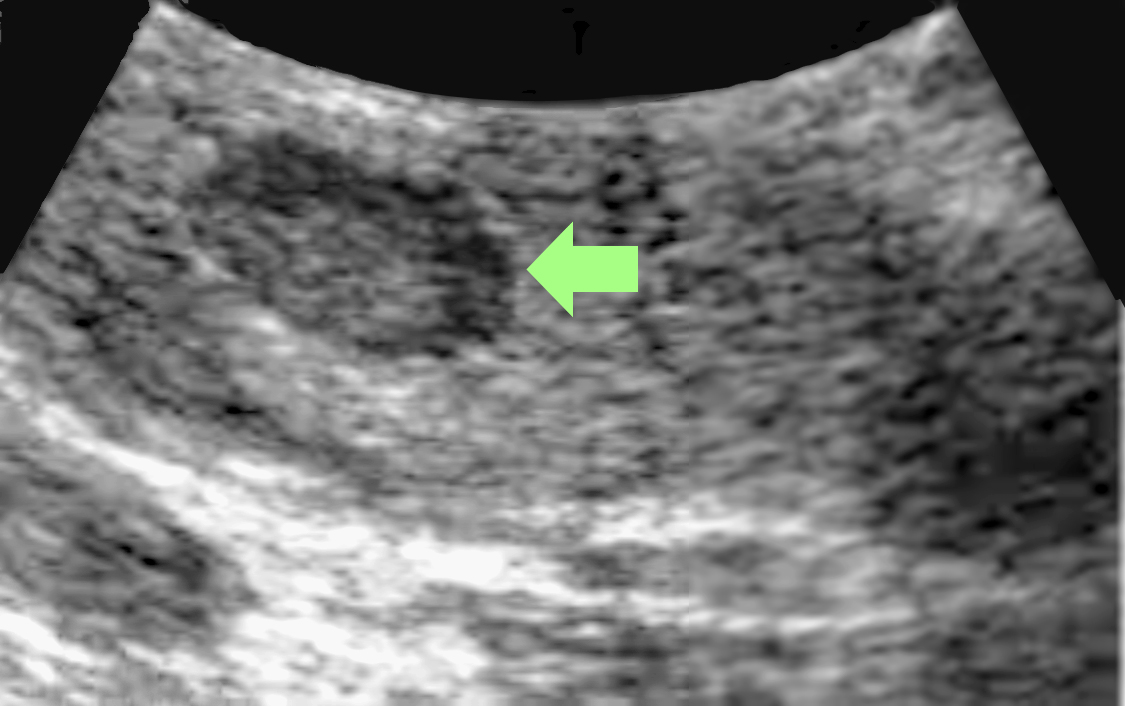

At Saint John’s Health Center and Cancer Institute, we take a complete medical history and do a physical exam before beginning any diagnostic procedures for pancreatic cancer. If pancreatic cancer is suspected, additional tests may be performed. Ultrasound (also called sonography) is a diagnostic imaging technique that uses high-frequency sound waves to create an image of the internal organs, specifically the liver, pancreas, spleen, and kidneys, and to assess blood flow through various vessels. The ultrasound may be done with either an external or internal device.

The images generated from ultrasound help us determine the size and location of a tumor in the pancreas and whether the tumor has spread to nearby blood vessels or other structures. Endoscopic ultrasound can also be used to obtain tissue samples. This is a type of biopsy called fine-needle aspiration. Cells obtained from the biopsy can then be analyzed more closely in a laboratory to see if they are cancerous.

Ultrasound

- Endoscopic ultrasound (EUS) is a procedure used to image the digestive tract, including the pancreas. A thin, flexible, lighted tube with a small ultrasound probe attached to the end is passed through the patient’s mouth into the stomach and the top part of the small intestine called the duodenum. The ultrasound component of the endoscope uses sound waves to create visual images of the pancreas.

- Transabdominal ultrasound involves placing an ultrasound device on the abdomen to create an image of the pancreas.